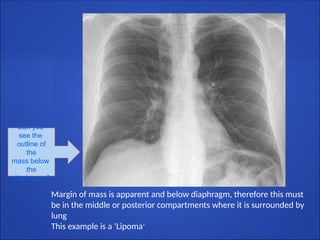

Thoracoabdominal sign

● A sharply marginated mediastinal mass seen through

the diaphragm must lie entirely within the chest.

● The posterior costophrenic sulcus extends far more

caudally than the anterior aspect of the lung

● Therefore

● Any mass that extends below the dome of the

diaphragm and remains sharply outlined must be in

the posterior compartments and surrounded by

lung, and

● Any mass that terminates at dome of diaphragm

must be anterior

Can you

see the

outline of

the

mass below

diaphragm?

Margin of mass is apparent and below diaphragm, therefore this must

be in the middle or posterior compartments where it is surrounded by

lung

This example is a ‘Lipoma’